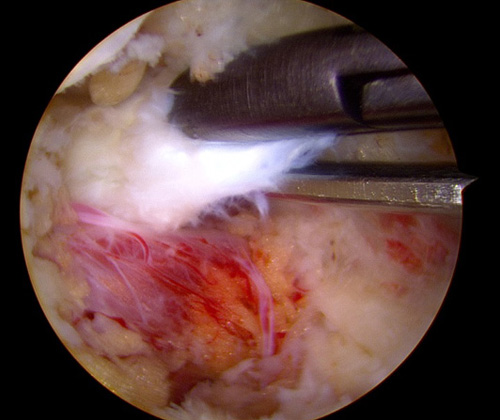

国内で施行されている脊椎内視鏡手術にはいくつかの方法があります。UBEはUnilateral Biportal Endscopic spine surgeryの略称で、BESSはBiportal Endoscopic Spine Surgeryの略称です。2つの呼び名がありますが、どちらも同じ手術方法です。カメラを挿入するための穴、手術器械を挿入するための穴、それぞれ5mm程度の小さな傷をあけ手術を行います。2つの穴から操作をしますので、手術の操作性が良好で、還流液がスムーズに流れ、良好な視野が得られることにより安全に手術が可能です。

UBE/BESSに対応可能な手術には腰椎椎間板ヘルニアのほか、腰部脊柱管狭窄症の除圧術、固定術があります。

いままでの脊椎内視鏡にはMEDと呼ばれているものがあり、約16mm径の筒を挿入して、その中で手術操作を行うものでした。体型の大きな方や脊柱のより深いところの治療を行う場合には操作性が悪いことがありました。一方、UBE/BESSは筒を挿入する必要はなく、直接カメラや手術機器を傷の中に入れて治療を行いますので、いままで届かなかった部位まで手術機器が届きます。また、操作性の自由度が非常に高いため、いままでの脊椎内視鏡手術で不可能であった治療も可能にしております。さらに、手術部位に生理食塩水を還流させながら行う手法で、細いカメラを直接病変部付近まで近づけることが可能なので、非常に良好な視野を得ながら安全に手術を行うことが可能です。

FESSの特徴

いままでの脊椎内視鏡にはMEDと呼ばれているものがあり、約16mm径の筒を挿入して、その中で手術操作を行うものでした。体型の大きな方や脊柱のより深いところの治療を行う場合には操作性が悪いことがありました。一方、FESSは8-10mm程度の傷で専用の器械を直接病変部位に挿入し、ヘルニアを切除したり神経組織の圧迫を取り除くことが可能です。手術によって損傷される背中の筋肉は最小限であり、術後の疼痛をできるだけ少なくすることが可能です。そのため、術後早期にリハビリが可能となり、仕事への早期復帰も実現可能です。

FESSで用いられるアプローチ方法

FESSで行う腰椎椎間板ヘルニアの手術には、インターラミナ法(IL法)、トランスフォラミナル法(TF法)などがあります。ヘルニアの発生部位などに応じて最も適した方法を選択します。